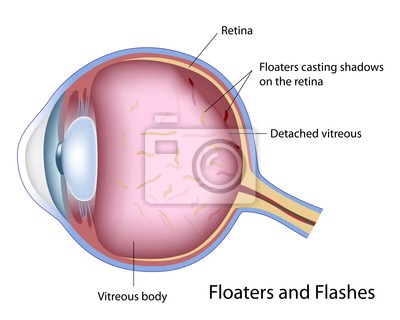

A:飛蚊症是指眼前有飄動的黑影,尤其是看白色背景的時候症狀更加明顯,同時有時候有些人會伴有閃光感,眼前一亮一亮的症狀,引起的原因主要是玻璃體液化和後脫離。絕大多數的飛蚊症都是生理性,但是有大約20%的飛蚊症,可能是病理性,具有威脅視力下降的情……

A:飛蠅症又稱飛蚊症和玻璃體混濁,是指玻璃體內出現不透明體,造成患者視物出現模糊。人出生時玻璃體呈凝膠狀態,是重要的屈光介質,正常的玻璃體隨著年齡逐漸出現液化,從而導致玻璃體混濁。此外,一切玻璃體混濁是由於病理原因所導致,例如玻璃體出血、葡萄……

A:眼前出現飛蚊的症狀往往是因為玻璃體發生了液化、變性和混濁,通常情況下玻璃體的混濁,比較多見於近視眼的人和年歲比較大的中老年人,還要特別重視的一個問題是當眼底有病變發生的時候,也會出現玻璃體的混濁、玻璃體混濁的加重,這時候眼前飛蚊的症狀需要做……

A:眼睛裡有飛蚊的現象主要是因為玻璃體發生了液化、變性和混濁,玻璃體原本在眼睛裡邊是一個膠凍狀的結構,由於近視眼以及中高度近視或者年齡過大了,中老年人就會出現玻璃體的液化、變性和混濁,這種情況下很難通過任何治療,將已經液化的玻璃體恢復到膠凍狀的……